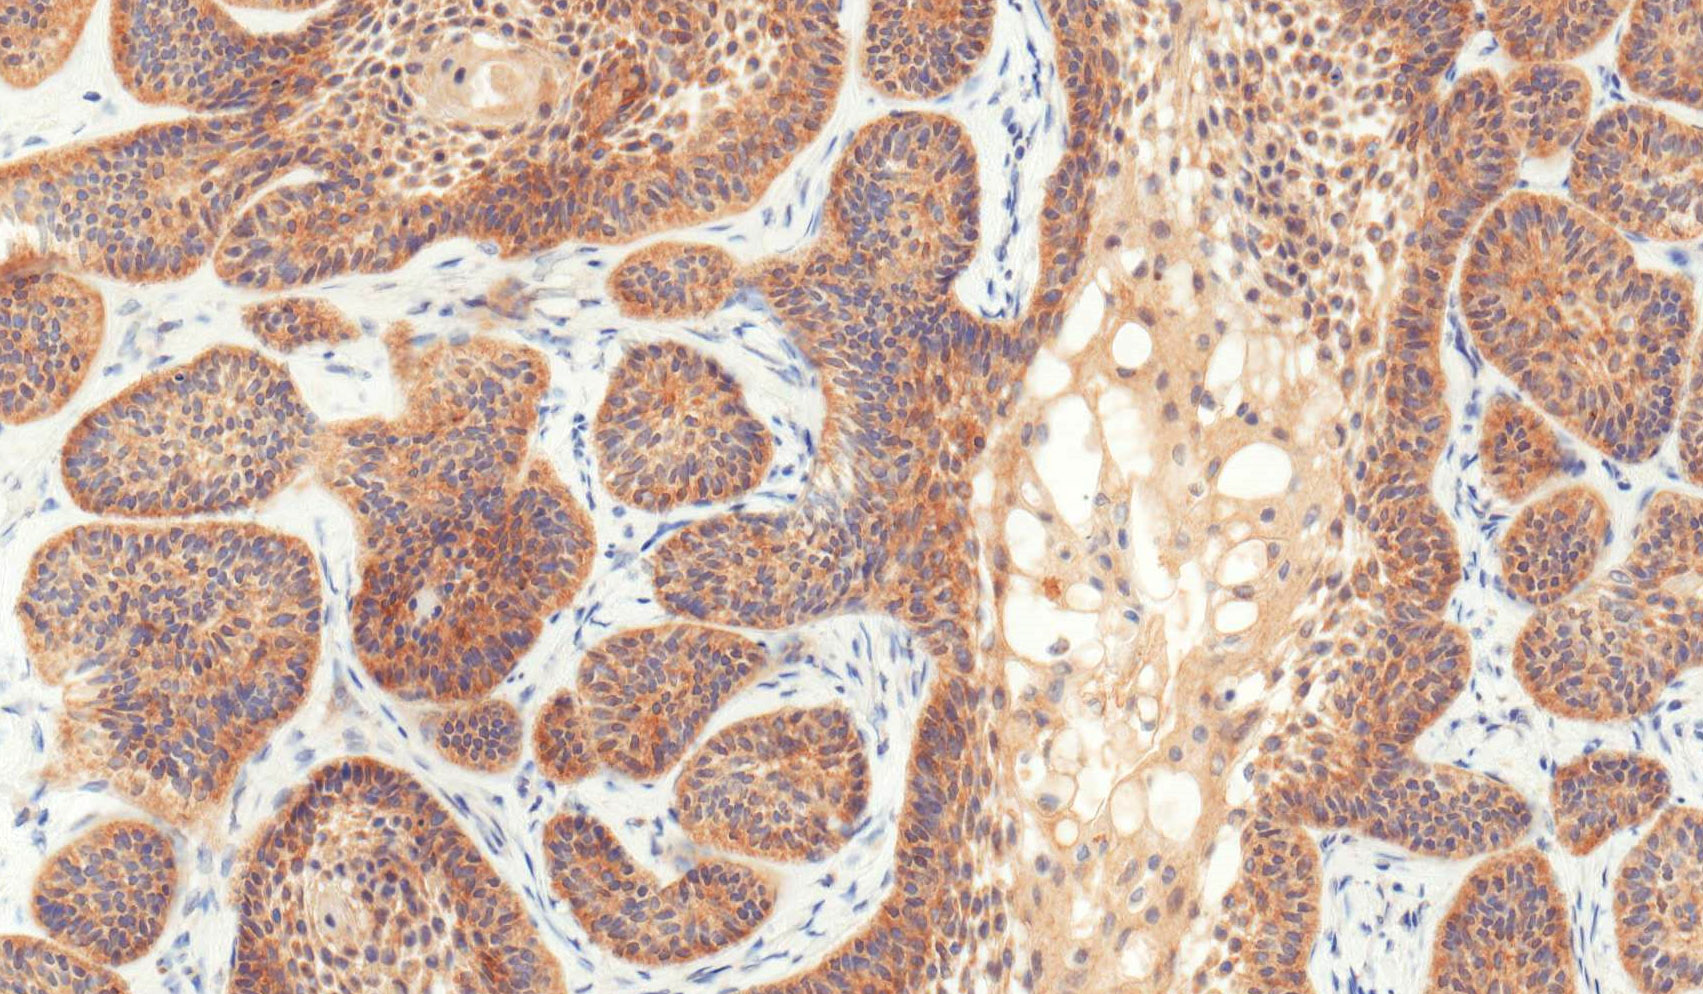

Microscopic (histologic) images

Contributed by Kelly Magliocca, D.D.S., M.P.H. and Anne C. McLean-Holden, D.M.D., M.S.

Microscopic (histologic) description

- Within the epithelial islands and cords of conventional ameloblastoma and the cystic epithelial lining of unicystic ameloblastoma, the odontogenic epithelium shows similar changes:

- Columnar cells with hyperchromatic nuclei at basal layer, exhibiting peripheral palisading

- Cells show reverse polarization away from basement membrane (Vickers-Gorlin change)

- Subnuclear vacuolization

- Suprabasal cells with a loose, network-like arrangement, recapitulating stellate reticulum formation seen in normal odontogenesis

- No dentin or enamel formation

- Ameloblastoma, conventional type has at least 6 histopathological patterns

- Follicular: most common subtype; islands of odontogenic epithelium in fibrous connective tissue; may be cystic; classic peripheral palisading and stellate reticulum-like areas